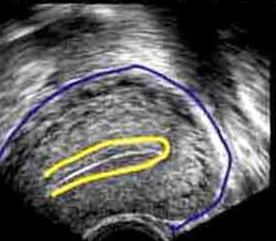

При дослідженні жінок в постменопаузі одним з найбільш важливих застосувань ультразвуку є діагностика і лікування раку ендометрію. Подібні дослідження дозволяють визначити нормальні розміри матки і яєчників по УЗД. І в цілому, внутрівагінальное УЗД перевершує можливості трансабдомінального для візуалізації міометрію та ендометрію.

При проведенні дослідження вимірюють не тільки розміри матки. По УЗД норма М-ехо – теж важливий показник. Він відображає розвиток, стан ендометрію і готовність його до прийому заплідненої яйцеклітини. Вимірюється він у різні фази циклу і має певні межі.

Під час менструації ендометрій з’являється як тонка эхогенная смужка 1-4 мм завтовшки, однак коливається від 4 до 8 мм в проліферативній фазі. В секреторній фазі після овуляції залози ендометрію стимулюються, і ендометрій з’являється як більш однорідна эхогенная смуга завтовшки від 8 до 15 мм.

Товщина внутрішньої оболонки 5 мм або менше є досить звичайною у жінок в постменопаузі і надійно виключає злоякісність у жінок. Однак товщина ендометрію до 8 мм може бути виявлена у жінок в постменопаузі, які отримували гормонотерапію. Варто врахувати подальші діагностичні дослідження у жінок в постменопаузі з товщиною ендометрія більше 8 мм, щоб виключити рак ендометрія.